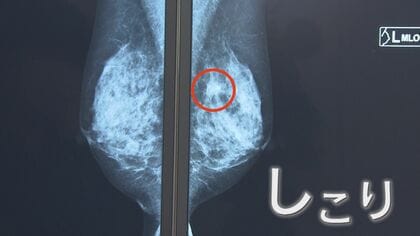

女性の9人に1人が「乳がん」に…最大の予防はやはり“検診” 両胸にがんが見つかった女性が語る「あの時一歩踏み出したから」

2023年10月17日